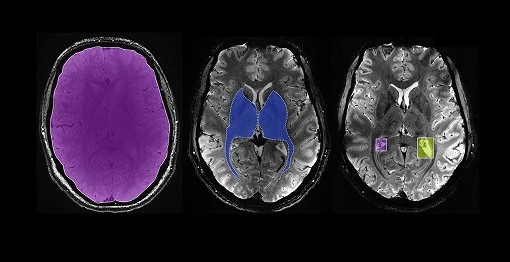

Medical image segmentation refers to the process of partitioning an image into meaningful regions, such as identifying organs, tumors, or lesions. This step is crucial because it enables AI models to focus on relevant structures, improving disease detection and treatment planning.

High-quality annotated datasets are the backbone of any supervised AI system. Annotation involves labeling regions or features in medical images, which trains AI algorithms to recognize and interpret similar patterns automatically. Building reliable AI datasets is essential for AI models to accurately detect patterns, improve diagnoses, personalize treatments, and reduce errors, ultimately enhancing patient outcomes and safety. Additionally, comprehensive datasets help ensure fairness by representing diverse populations, support regulatory compliance, and drive innovation and trust in AI-driven healthcare solutions.